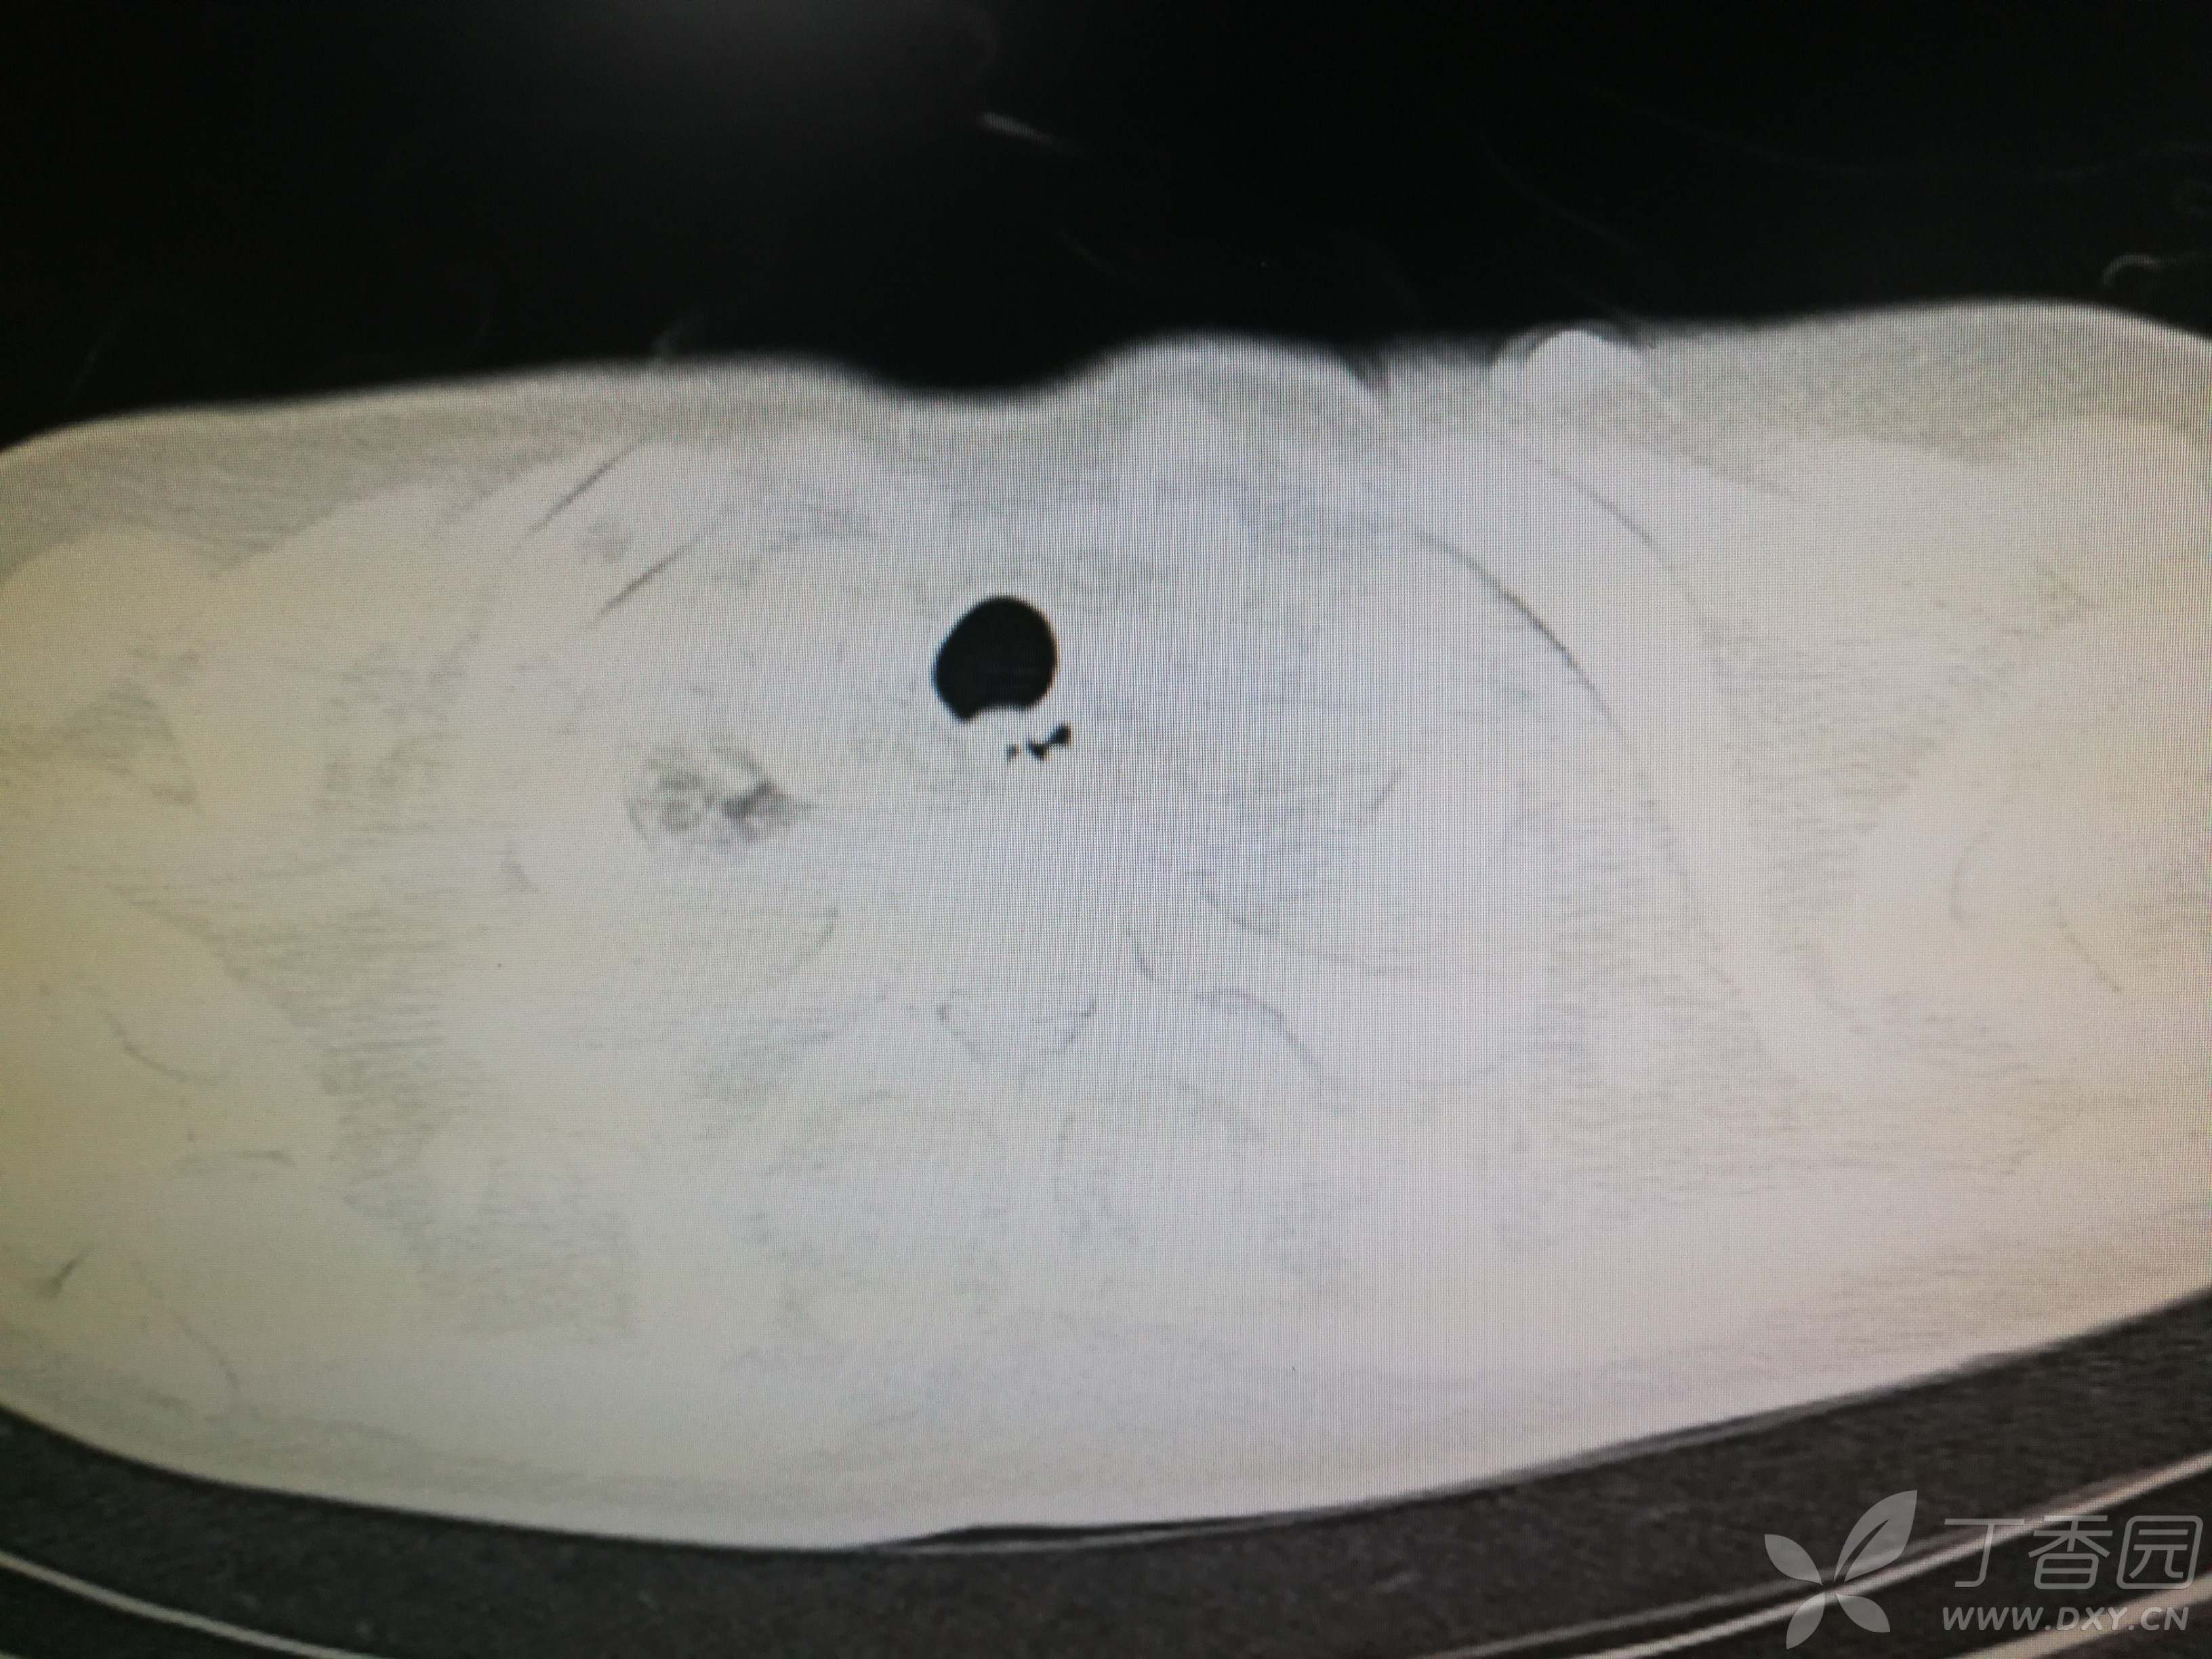

给予低分子肝素钙针抗凝、七叶皂苷钠针消肿及骨牵引固定等等治疗。入院后第四天行“左侧股骨下段骨折切开复位内固定术”(术前查双下肢彩超:双下肢深静脉血流通畅),手术顺利,术后予预防感染、预防血栓形成等治疗。术后患者无明显发热,生命体征平稳。术后第四天复查血常规:白细胞13.4×109/L,血红蛋白84g/L,血小板在正常范围。生化:白蛋白35.7g/L,余无明显异常。当天,患者开始出现轻度胸闷气急,可耐受。术后第五天患者胸闷气急加重,无胸痛,无背痛,无咯血,无意识障碍,无头晕头痛,无恶心呕吐等,急查凝血功能:纤维蛋白原降解产物12mg/L,D二聚体4000ug/L,余无明显异常。查动脉血气分析:pH7.52,氧分压62mmHg,二氧化碳分压30mmHg,碱剩余1.8mmol/L,乳酸1.0mm/L,血红蛋白86g/L。查胸部CT见下(先视频后图片):